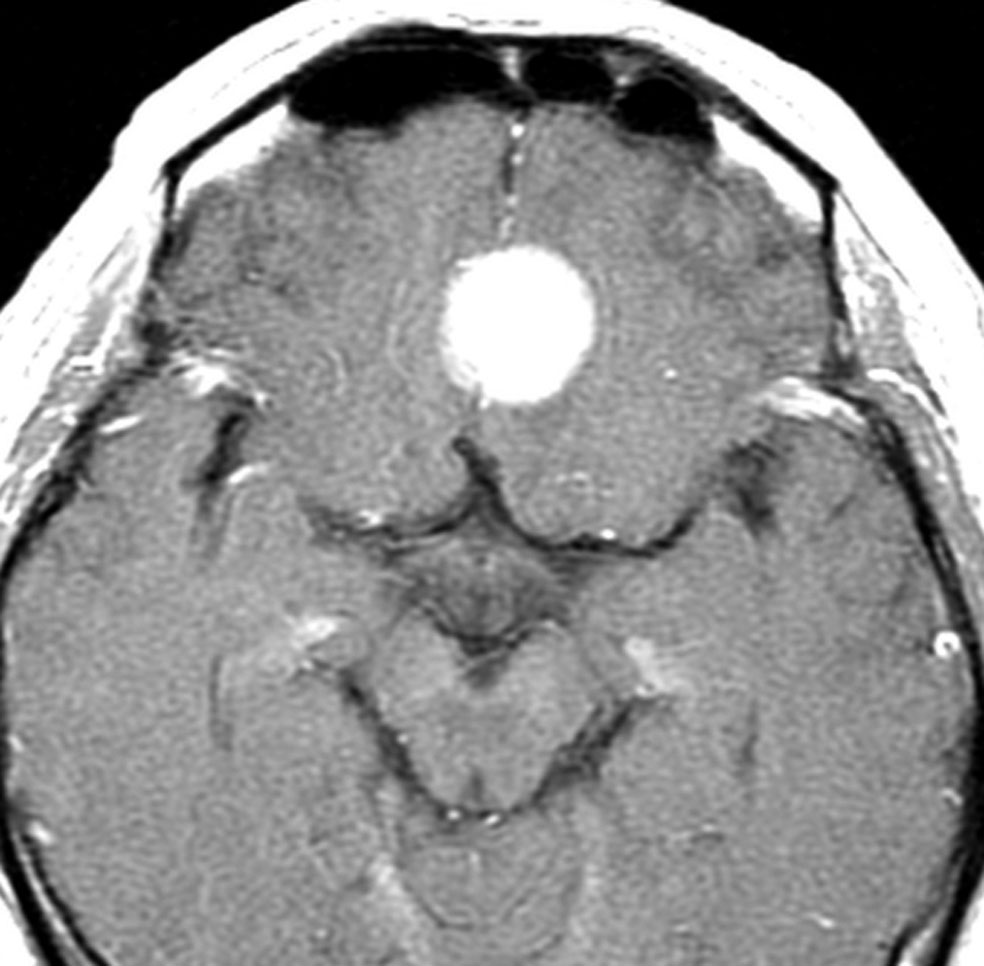

- ガドリニウム造影剤で,髄膜腫がはっきりみえます(コントラストがついて白く見えます)

左は,造影剤を使ったガドリニウム増強MRIです。腫瘍が白く丸く見えます。右はフレア画像で,腫瘍の周囲の脳浮腫(脳のはれ)です。左前頭葉が,かなり強くはれています。この腫瘍は小さいのですが,脳のはれが強すぎるので手術摘出したほうがいいです。浮腫が悪化すると,てんかん発作や認知機能低下がでる可能性があります。

最も見やすいのが,ガドリニウム造影剤を注射して撮影するものです。一般的に髄膜腫は造影剤で白く映し出されます。この腫瘍は左脳側にあります。MRIの軸面という輪切りの写真では左右が逆になりますから注意してください。脳を下から見た図になっています。MRIはいろいろな方向から腫瘍を見ることができますが,右は冠状断という正面から見た図です。よく見ると腫瘍の上と下のはじっこに線状に糸を引いたように造影される部分があります。これをテールサイン(しっぽのサイン)といいます。腫瘍が硬膜に沿って延びている可能性があることを示しています。